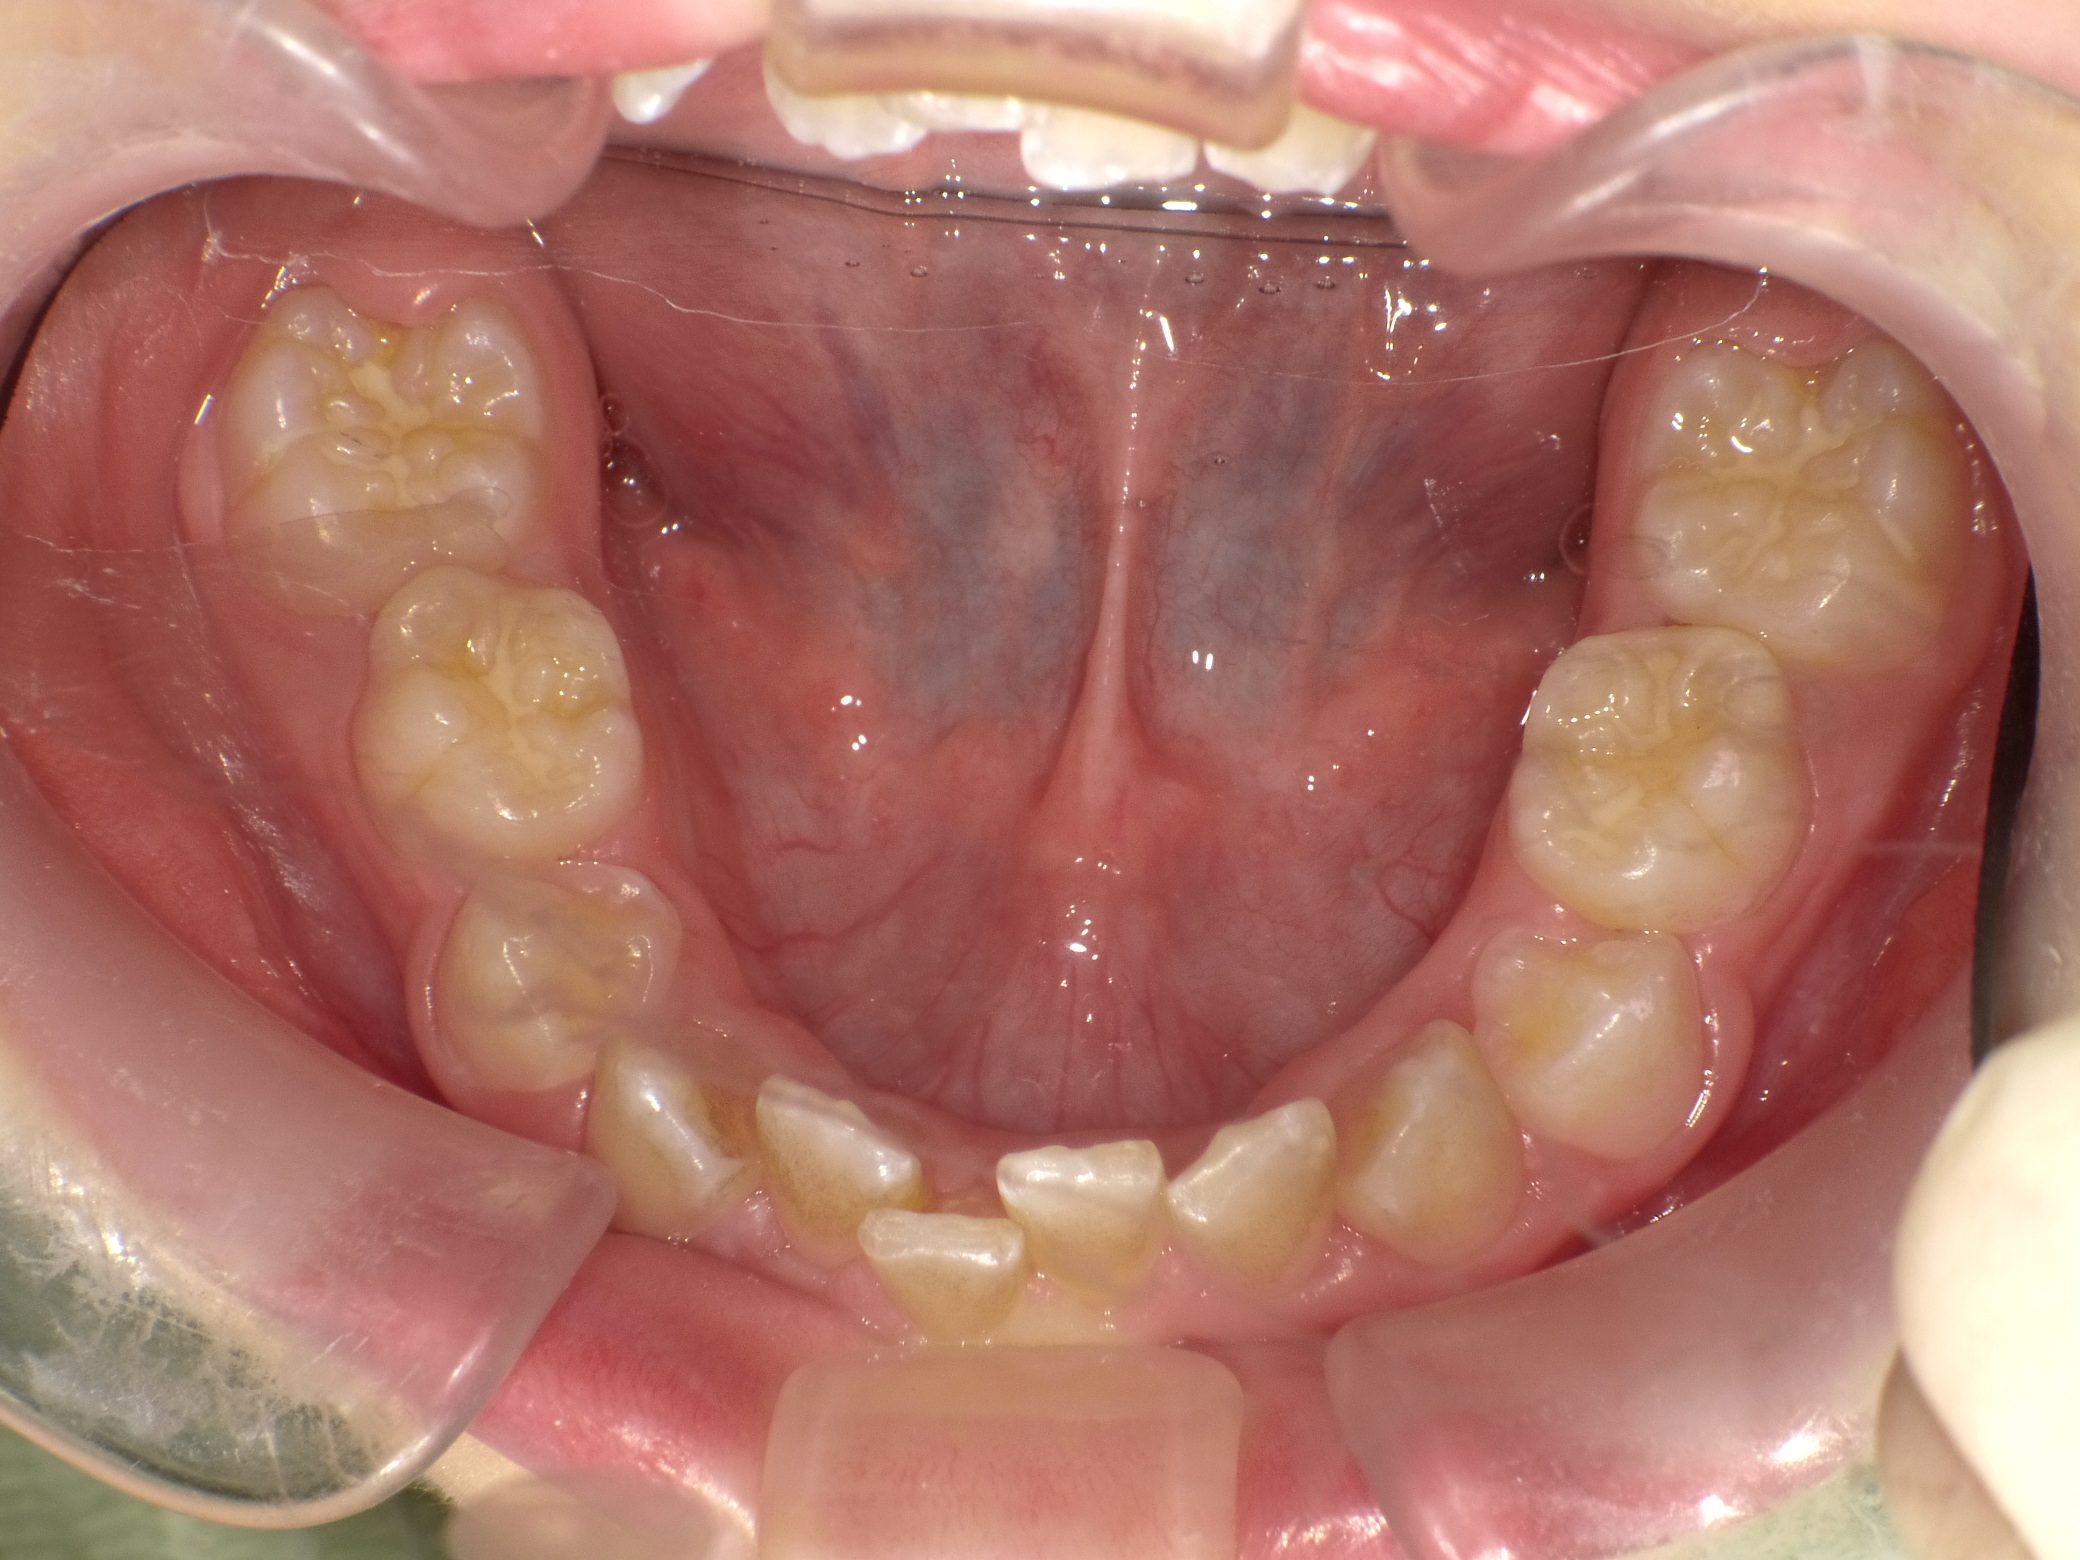

Before

After

【小学生】10歳 マイオブレース矯正 叢生(でこぼこ)と過蓋咬合(深い咬み合わせ)を改善

かなりきちんと取り組んでくれたので、機能矯正装置と MFT(筋機能療法)のみで 改善しています。

機能矯正装置のみで改善するかどうかは もともとの歯並び + 患者さんの装置の使用状況 MFTへの取り組み状況により

変わります。